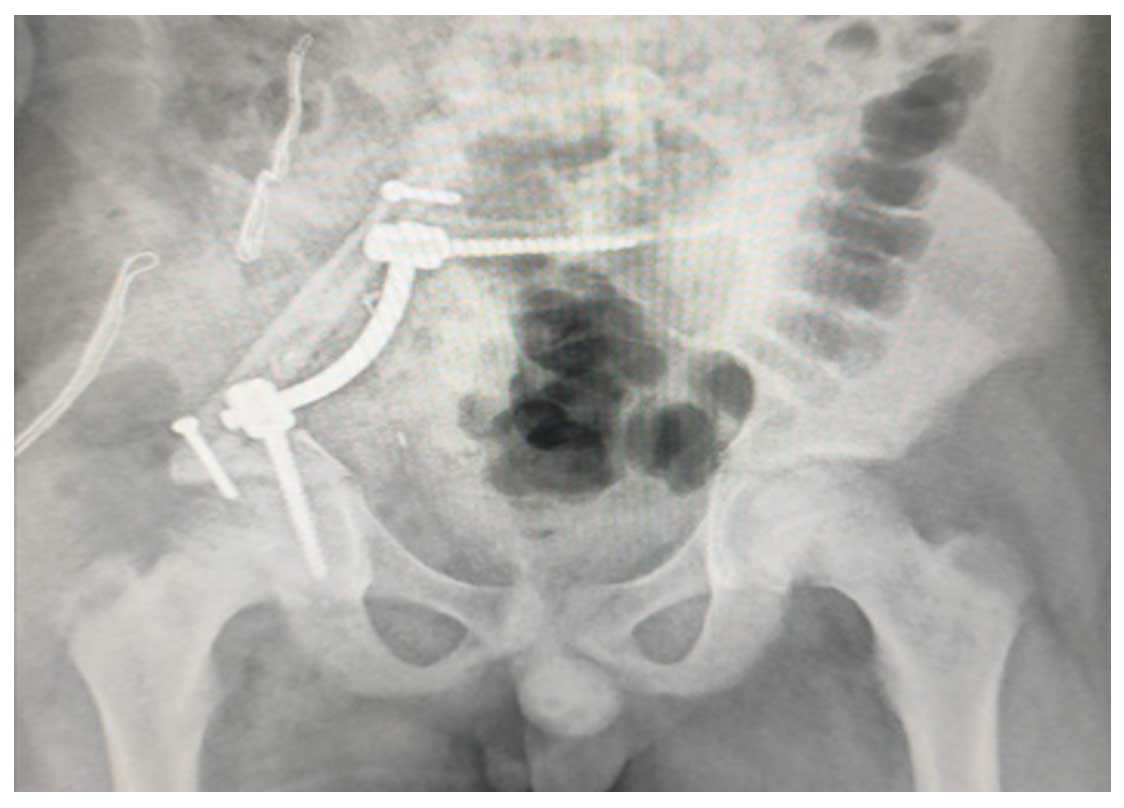

Ameliyat Esnası: Rezeksiyon sonrası nörovasküler yapıların korunduğu, fibula ve rod/vida ile rekonstrüksiyon uygulanımı görülmekte.

Ameliyat Sonrası: İnternal hemipelvektomi sonrası fibula ve rod/vida ile lumbopelvik fiksasyon uygulanımı görülmekte.